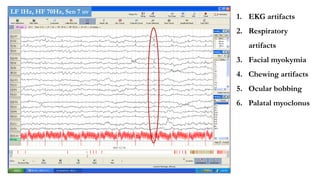

Non cerebral causes of GPD

1. EKG artifacts

2. Respiratory

artifacts

3. Facial myokymia

4. Chewing artifacts

5. Ocular bobbing

6. Palatal myoclonus

LF 1Hz, HF 70Hz, Sen 7 uv